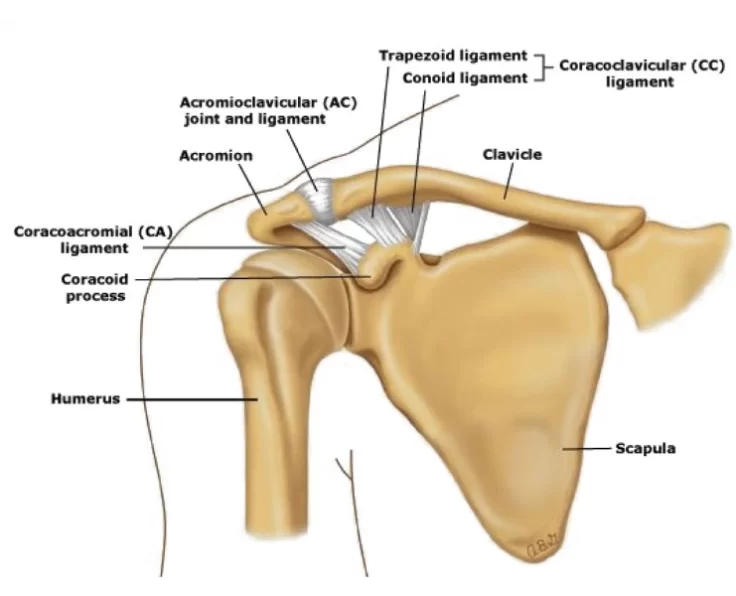

AC Joint Reconstruction

The acromioclavicular joint, often known as the AC joint, is positioned on the top of the shoulder, where the clavicle (collarbone) meets the acromion (shoulder…

AC Joint Excision

The goal of the procedure is to remove the uncomfortable and injured Acromioclavicular Joint (ACJ) without causing it to become unstable.